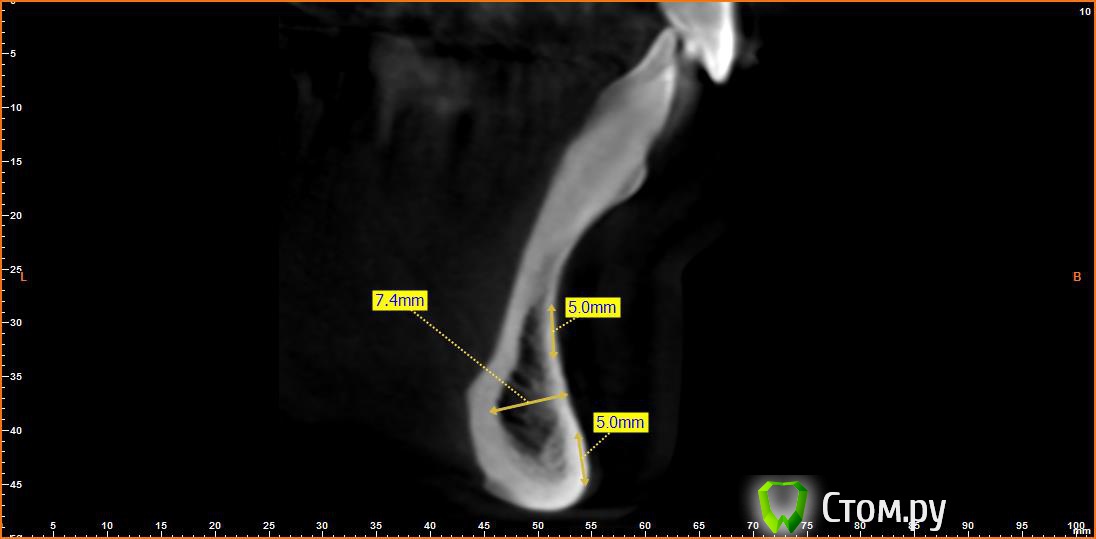

Opimar Опубликовано 21 июня, 2014 Автор Поделиться Опубликовано 21 июня, 2014 Выкладываю еще. Пошагово от 34-37 Ссылка на комментарий

Bier Опубликовано 21 июня, 2014 Поделиться Опубликовано 21 июня, 2014 Выкладываю еще. Пошагово от 34-37темная точка достаточно высоко, это по моему не нерв, нерв ниже, я правильно понимаю? Ссылка на комментарий

Opimar Опубликовано 21 июня, 2014 Автор Поделиться Опубликовано 21 июня, 2014 темная точка достаточно высоко, это по моему не нерв, нерв ниже, я правильно понимаю?Да он ниже и язычнее. Провел от менталиса там еще запас есть. Ссылка на комментарий